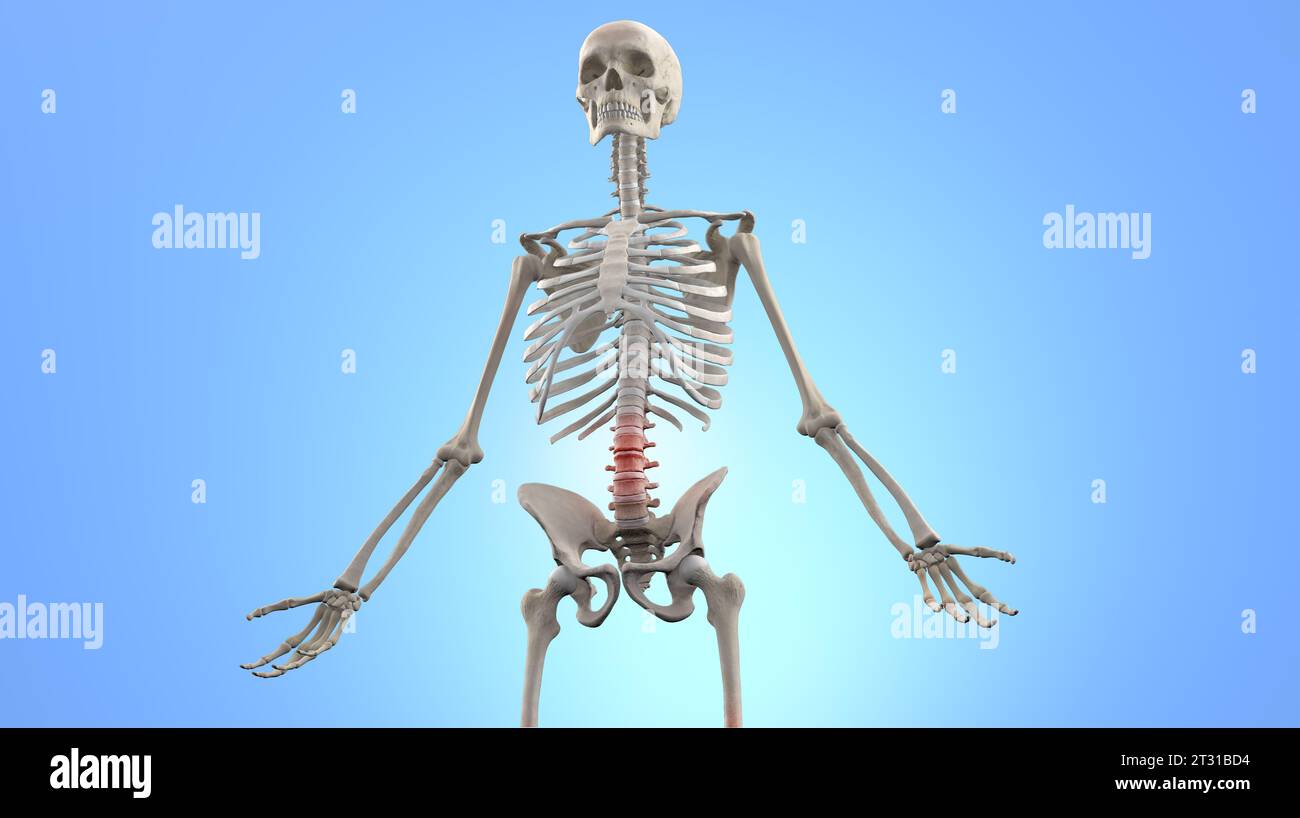

Anatomy of Human Spine. Lower back pain and human backache Stock Photohttps://www.alamy.com/image-license-details/?v=1https://www.alamy.com/anatomy-of-human-spine-lower-back-pain-and-human-backache-image569817056.html

Anatomy of Human Spine. Lower back pain and human backache Stock Photohttps://www.alamy.com/image-license-details/?v=1https://www.alamy.com/anatomy-of-human-spine-lower-back-pain-and-human-backache-image569817056.htmlRF2T31BD4–Anatomy of Human Spine. Lower back pain and human backache